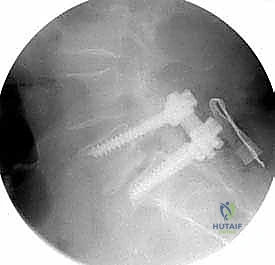

عملية دمج الفقرات (Spinal Fusion) هي إجراء جراحي يهدف إلى ربط فقرتين أو أكثر بشكل دائم، مما يزيل الحركة غير الطبيعية والمؤلمة بينهما، ويعيد الاستقرار الميكانيكي إلى العمود الفقري. في حالتنا هذه، يتم التركيز بشكل خاص على المنطقة الصدرية القطنية (Thoracolumbar Junction)، وهي المنطقة الانتقالية الحرجة التي تربط الجزء العلوي من الظهر (القفص الصدري الصلب) بالجزء السفلي (المنطقة القطنية المتحركة). يتم التثبيت باستخدام أدوات طبية معدنية متطورة (Instrumentation) مثل المسامير السويقية (Pedicle Screws) والقضبان المصنوعة من التيتانيوم.

تعتبر السويقة الفقارية (Pedicle) جسرًا عظميًا أسطوانيًا يربط الأجزاء الخلفية للفقرة (القوس الفقري) بالجسم الفقري الأمامي الضخم. في جراحة دمج الفقرات الحديثة، تعتبر السويقة نقطة التثبيت الرئيسية والأقوى للمسامير المستخدمة في العملية (Pedicle Screws). يختلف شكل وحجم وزاوية السويقات بشكل كبير على طول العمود الفقري، وفهم هذه الفروق الدقيقة أمر بالغ الأهمية للجراح لضمان وضع المسامير بأمان تام وفعالية قصوى دون الإضرار بالأعصاب أو الأوعية الدموية.

* التصوير المقطعي المحوسب (CT Scan): يوفر صوراً ثلاثية الأبعاد للعظام، وهو ضروري جداً للتخطيط الجراحي الدقيق وتحديد أحجام المسامير المناسبة لكل سويقة فقارية.